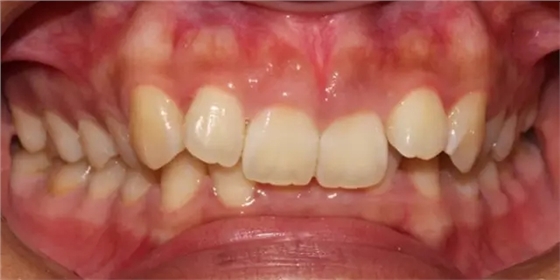

患者側(cè)面凸,鼻唇角較銳,笑時(shí)露齦笑明顯上下牙列擁擠,磨牙尖牙Ⅱ 類關(guān)系,3 度的深覆牙合,上頜中切牙伸長內(nèi)傾拔除上頜雙側(cè)的第一前磨牙,先粘上頜高轉(zhuǎn)矩的自鎖托槽排齊牙列,唇向開展上頜切牙,有一定的覆蓋,粘下頜標(biāo)準(zhǔn)轉(zhuǎn)矩托槽,上頜 1, 2 之間植入種植支抗壓入,同時(shí)后牙 5, 6 之間植入種植支抗內(nèi)收前牙,打開咬合關(guān)閉間隙。治療關(guān)鍵:前牙轉(zhuǎn)矩的控制第 1 個(gè)月 上頜粘上 Damon Q 高轉(zhuǎn)矩托槽,上 .014 熱激活 NiTi 絲。第 3 個(gè)月 上換 .014 x .025 熱激活 NiTi 絲。第 5 個(gè)月 上頜基本排齊,覆蓋增大,上換 .017 x .025 NiTi絲,下頜粘托槽,下 .014 熱激活 NiTi 絲。第 7 個(gè)月 上 .017 x .025 NiTi 絲加搖椅,下?lián)Q .014 x .025 熱激活 NiTi 絲第 9 個(gè)月 上頜換 .019 x .025 NiTi 絲加搖椅,下頜換 .017 x .025 NiTi 絲第 11 個(gè)月 下頜換 .019 x .025 加搖椅,上頜 1, 2 之間, 5, 6 之間植入種植釘,下頜出現(xiàn)散隙。第 13 個(gè)月 上頜換 .019 x .025ss 加搖椅,前牙種植釘用 Power Chain 壓低前牙(每側(cè) 100g),后牙種植釘關(guān)閉間隙(每側(cè) 150g),下?lián)Q .019 x .025ss,Power Chain 關(guān)閉間隙。第 19 個(gè)月 上頜前牙基本壓低到位去除前牙種植釘,繼續(xù)用關(guān)閉間隙,下頜散隙關(guān)閉。

第 22 個(gè)月 上頜覆蓋變小,去除 5, 6 之間種植釘,后牙前移關(guān)閉間隙。第 30 個(gè)月 患者未配合中線牽引,下中線仍有 1mm 右偏,患者對矯治效果滿意要求拆除,拆除固定矯治器,取模制作壓模保持器。 1.骨性 Ⅱ 類的患者內(nèi)收前牙時(shí)需對上頜前牙的轉(zhuǎn)矩進(jìn)行較好的控制才能獲得良好的面型和唇部形態(tài)。 2.露齦笑的患者治療前要分析其病因是唇、牙齦、牙齒、牙槽骨、上頜骨或多種因素結(jié)合,再制定矯治方案。 3.Ⅱ 類第二分類伴露齦笑的患者的上頜前牙移動軌跡是唇向開展-壓低-整體內(nèi)收。 4.Ⅱ 類第二分類牙齒舌傾比較厲害的情況,上頜中切牙慎用樹脂咬合墊。 5.壓低前牙或控根移動時(shí)容易發(fā)生牙根的吸收,需輕力緩慢的移動。